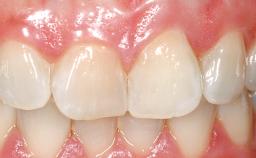

Early Placement of an Implant in a Maxillary Right Central Incisor Site

This 41-year-old female patient was referred to the clinic for the replacement of the right central incisor, since the tooth had developed a root fracture in the long axis that made extraction necessary. The healthy, non-smoking patient was first seen with the tooth still in place. A detailed Esthetic Risk Assessment was performed.The patient was worried about her dental esthetics and had high expectations for a successful treatment outcome from an esthetic point of view. The patient had a medium lip line that displayed parts of the gingiva in the anterior maxilla upon smile.

Patient's Esthetic Expectations Low Medium High

Lip Line No exposure of papillae Exposure of papillae Full exposure of mucosa margin

Soft Tissue Anatomy Intact Defective